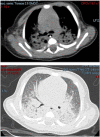

Severe acute respiratory syndrome coronavirus 2 (SARS-CoV-2), the etiological agent of coronavirus disease 2019 (COVID-19), may manifest as a life-threatening respiratory infection with systemic complications. Clinical manifestations among children are generally less severe than those seen in adults, but critical cases have increasingly been reported in infants less than 1 year of age. We report a severe case of neonatal COVID-19 requiring intensive care and mechanical ventilation, further complicated by a multidrug-resistant Enterobacter asburiae super-infection. Chest X-rays, lung ultrasound, and chest computed tomography revealed extensive interstitial pneumonia with multiple consolidations, associated with persistent increased work of breathing and feeding difficulties. SARS-CoV-2 RNA was detected in respiratory specimens and stools, but not in other biological samples, with a rapid clearance in stools. Serological tests demonstrated a specific SARS-CoV-2 antibody response mounted by the neonate and sustained over time. The therapeutic approach included the use of enoxaparin and steroids which may have contributed to the bacterial complication, underlying the challenges in managing neonatal COVID-19, where the balance between viral replication and immunomodulation maybe even more challenging than in older ages.